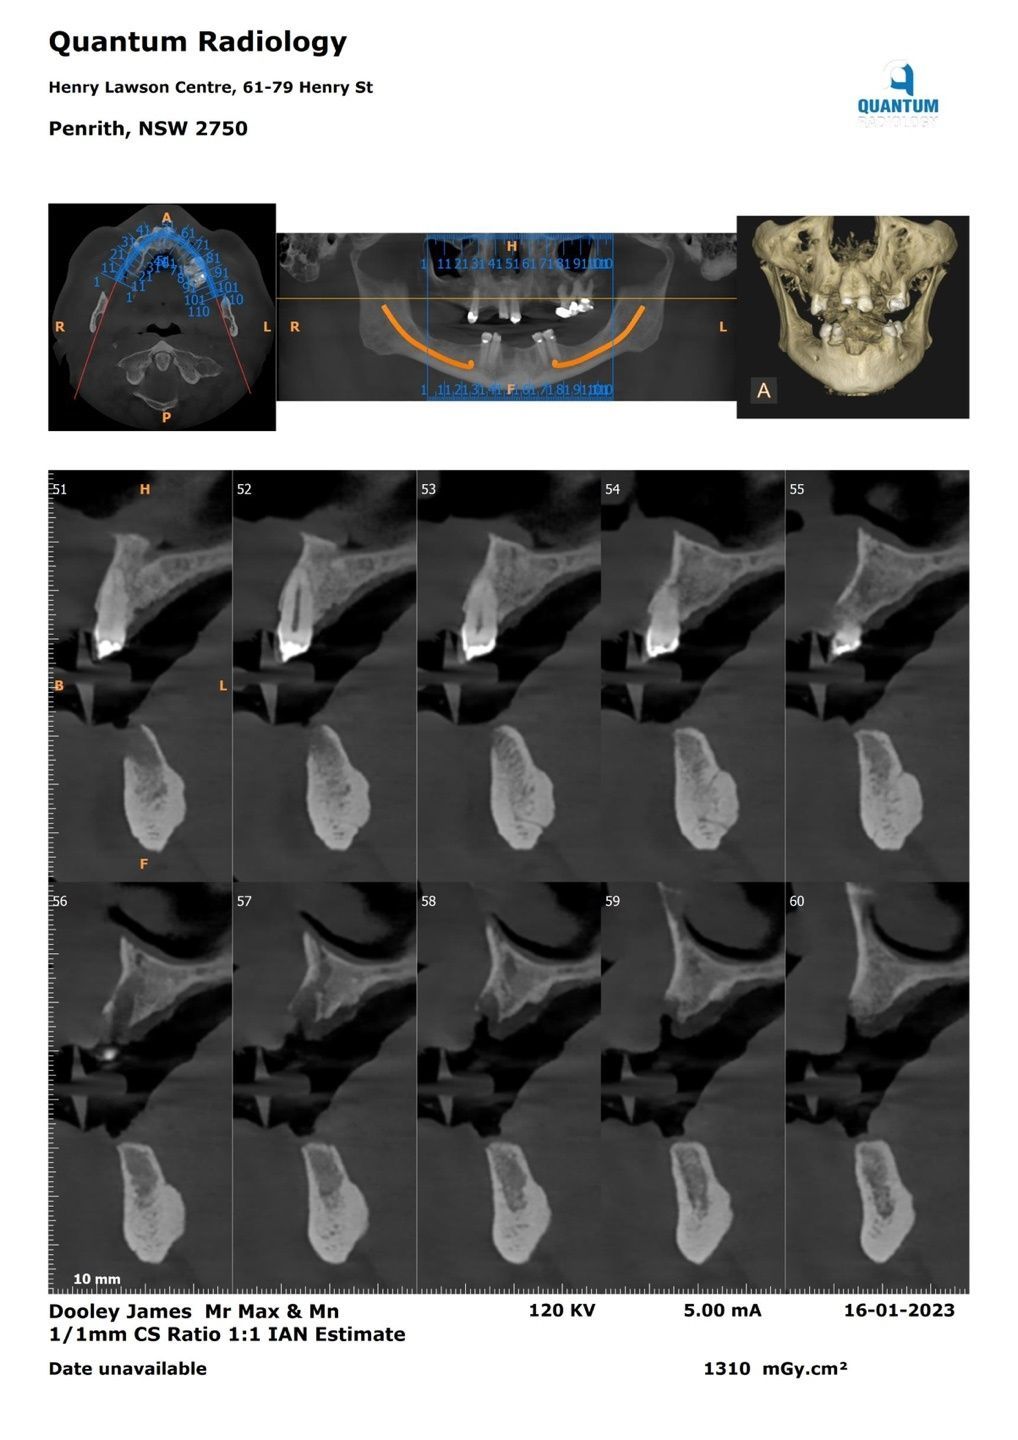

CT imaging revealed areas in the maxilla where bone height was insufficient,

indicating that bone augmentation (bone grafting) would likely be required before implant placement.

This view shows the analysis used to determine the optimal positions,

angulations, and depths for implant placement in both the maxilla

and mandible in a fully edentulous case.

In the maxilla, the location of the maxillary sinus is a key factor,

while in the mandible, the position of the inferior alveolar nerve canal is critical.

If the bone quality is insufficient,

bone grafting may be required to achieve stable implant placement.